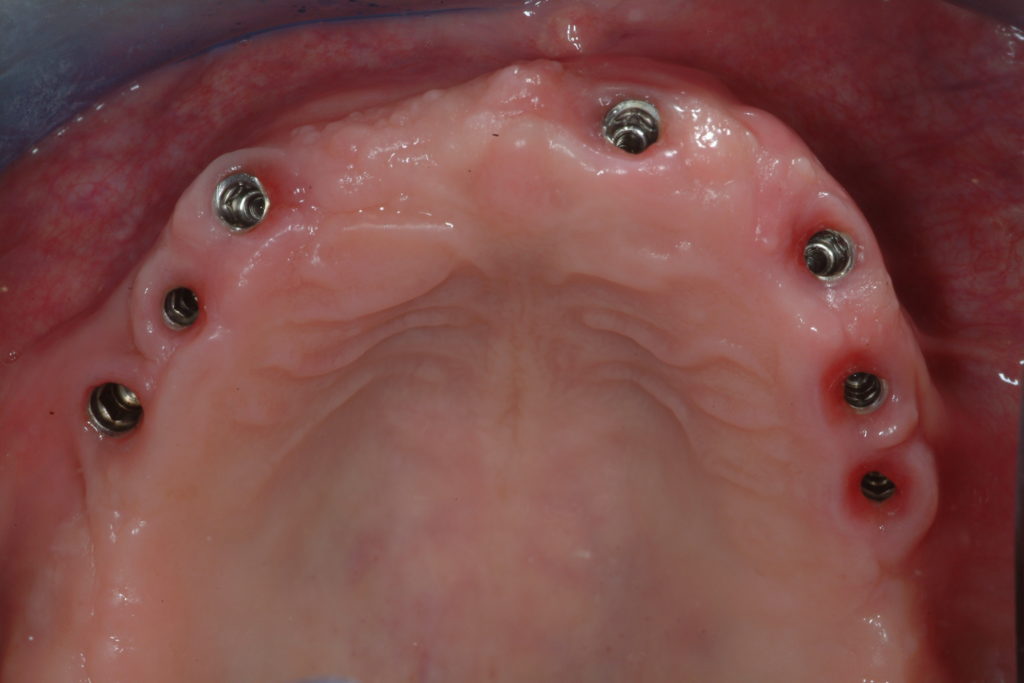

Mobile dentures on implants

In the case of a completely toothless (edentulous) patient, a removable prosthesis, the so-called dentures, can be used. Classic dentures have a support on the gum and therefore little stability.

To improve the stability of the dentures, we can use two to six implants. The dentures will be able to rest on the implants through Teflon or metal attachments and obtain considerable stability during chewing.

By pulling lightly, the patient can easily remove the dentures and brush them at the end of each meal. In the same way, she/he will be able to clean the implants that are non-other than the pillars of the dentures.

Clinical cases